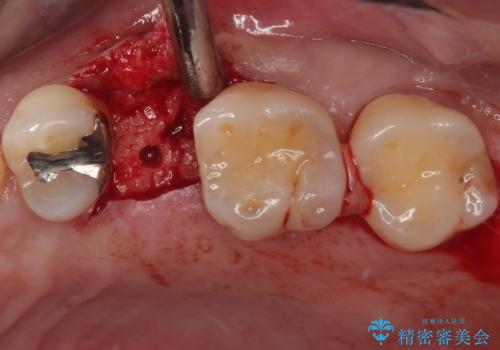

- むし歯で抜歯したまま放置していたとのことで来院された患者様です。

仕事が忙しいことと、外科手術が怖いとのことで歯科医院を避けていたものの、当院の1DAYインプラント治療を見て、重い腰を上げて来院されたとのことでした。

事前に仮歯を用意し、インプラント埋入時に仮歯を装着し、その後歯肉の治りを待って速やかにオールセラミッククラウンにて補綴治療を行うこととしました。

インプラント埋入時に十分な安定性が確認できたため、当日仮歯を装着しました。